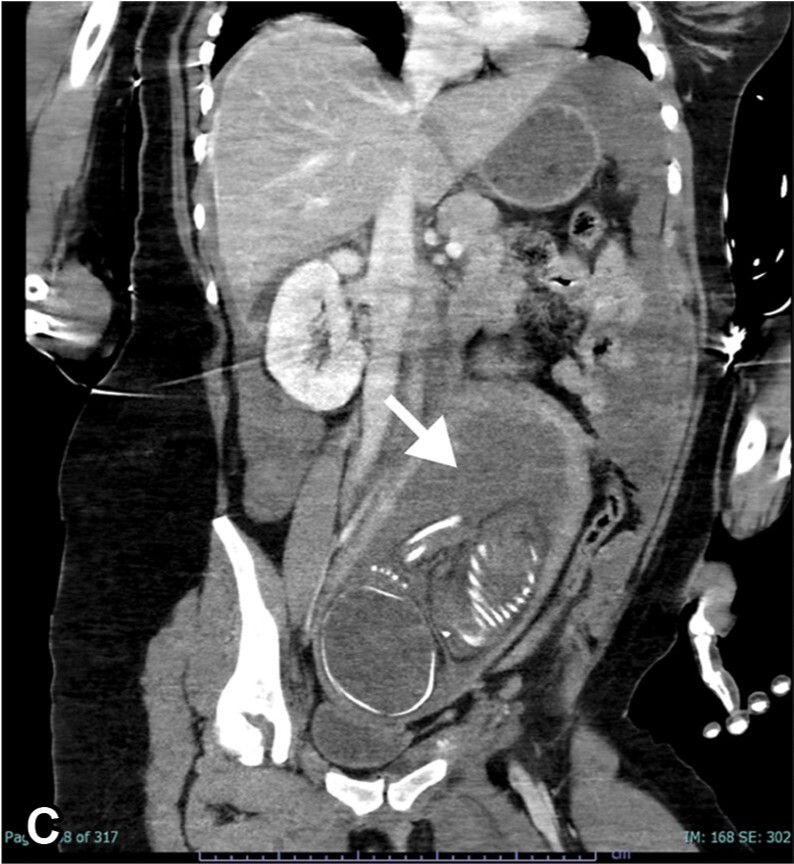

Trauma in pregnancy is critical — two patients, one priority: save the mother to save the baby. CT shouldn’t wait when needed. With proper protocols, the benefits far outweigh the risks. @YaleMed @YaleRadiology @DrJonLangdon https://t.co/wDI6UEJhGv